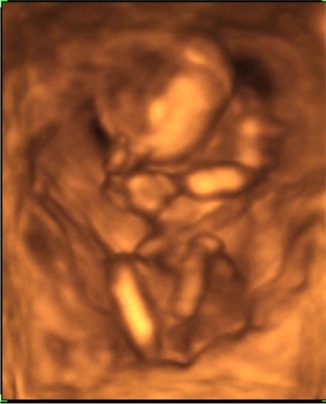

Megjöttünk a 4D-ről :) :) :)

Nagyon nagyon jó volt! Csúcsszuper :D

A babucim iszonyú jól érzi magát odabent, fészkelődik, rugdalózik megállás nélkül, ugyanúgy mint a 12 hetesen :lol:

Fejétől a lábujjáig 13cm .. persze ennél kisebb helyet foglal, mert fel van húzva a lába ..stb.

10,2 dkg a Lelkem :)

Láttuk a kis szívét, a 4 szívkamrát, az agyát... az agyféltekéket, a gyomrát, a húgyhólyagját .. szóval messze felülmúlta a vizsgálat minden várakozásunkat.

A csöppség nemét nem merték biztosra mondani, így ezzel kapcsolatban még izgulhatunk kicsit :lol: :lol:

A 2D alapján kislányt mondanának .. de a 4D-n néha láttunk gyanus elemeket. De az lehetett a szeméremajkak is .. mert ebben az időszakban még azok is csúcsosak :) nah majd kiderül időben :) A nő szerint ebben az időszakban még nem lehet 100%-osra mondani, ő nem szeret jósolgatni.

A pici hasamnak viszont megvan az oka .. a hátrahajló méhem egy dolog, de abban is leghátul, lent a medencémben fészkelte be magát a babuci, így egészen a szeméremcsontomhoz kellett bekukkantanunk .. és nagyon nehezen tudtuk őt követni. De szerencsére egyfolytában mozgott .. így mindenét meg tudtuk nézni, és elkaptunk nagyon jó pillanatokat!

A kiskönyvemben április 9re vagyok kiírva, ha a hosszú ciklust belekalkulálom, akkor április 13. Na az első UH-n április 19-et mondtak (ez 8 hetesen volt), aztán a 12 hetesen április 13-at, most pedig április 14-et :) :) Nagy különbségek nincsenek, így rendben fejlődik a Drága!!!!

Boldogság van!!!

Mindjárt megpróbálok fotót mutatni róla!

Kép \"mutatom az arcocskám\"

Kép \"vakarom a fejecském\"

Kép \"látjátok hogy tornázom?\"

Kép \"elfáradtam ... hátrabújok pihenni\"